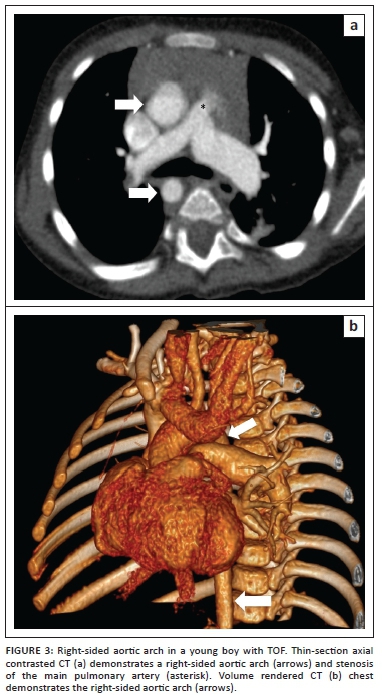

Preoperative imaging is directed at confirmation of the diagnosis and differentiation of TOF from other common mixing disorders such as a common arterial trunk, transposition of the great vessels with a ventricular septal defect or a double-outlet right ventricle (DORV). Further goals of preoperative imaging are to establish the severity of the primary anatomical lesion, the associated anomalies and the degree of functional disturbance, that in turn dictate appropriate timing of surgical intervention - either definitive early repair or a staged approach following initial palliation. The surgical approach itself may be altered by anatomical relationships of cardiac, coronary and extra-cardiac structures, such as a right-sided aortic arch (Figure 3), MAPCAs and variant coronary anatomy.11 The debate around timing of surgery and the multitude of institutional preferences of surgical approach is beyond the scope of the present paper.